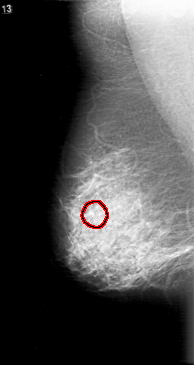

D_4100_1.RIGHT_MLO

FILE: D_4100_1.RIGHT_MLO.OVERLAY

TOTAL_ABNORMALITIES 1

ABNORMALITY 1

LESION_TYPE CALCIFICATION TYPE PUNCTATE DISTRIBUTION CLUSTERED

ASSESSMENT 0

SUBTLETY 1

PATHOLOGY BENIGN